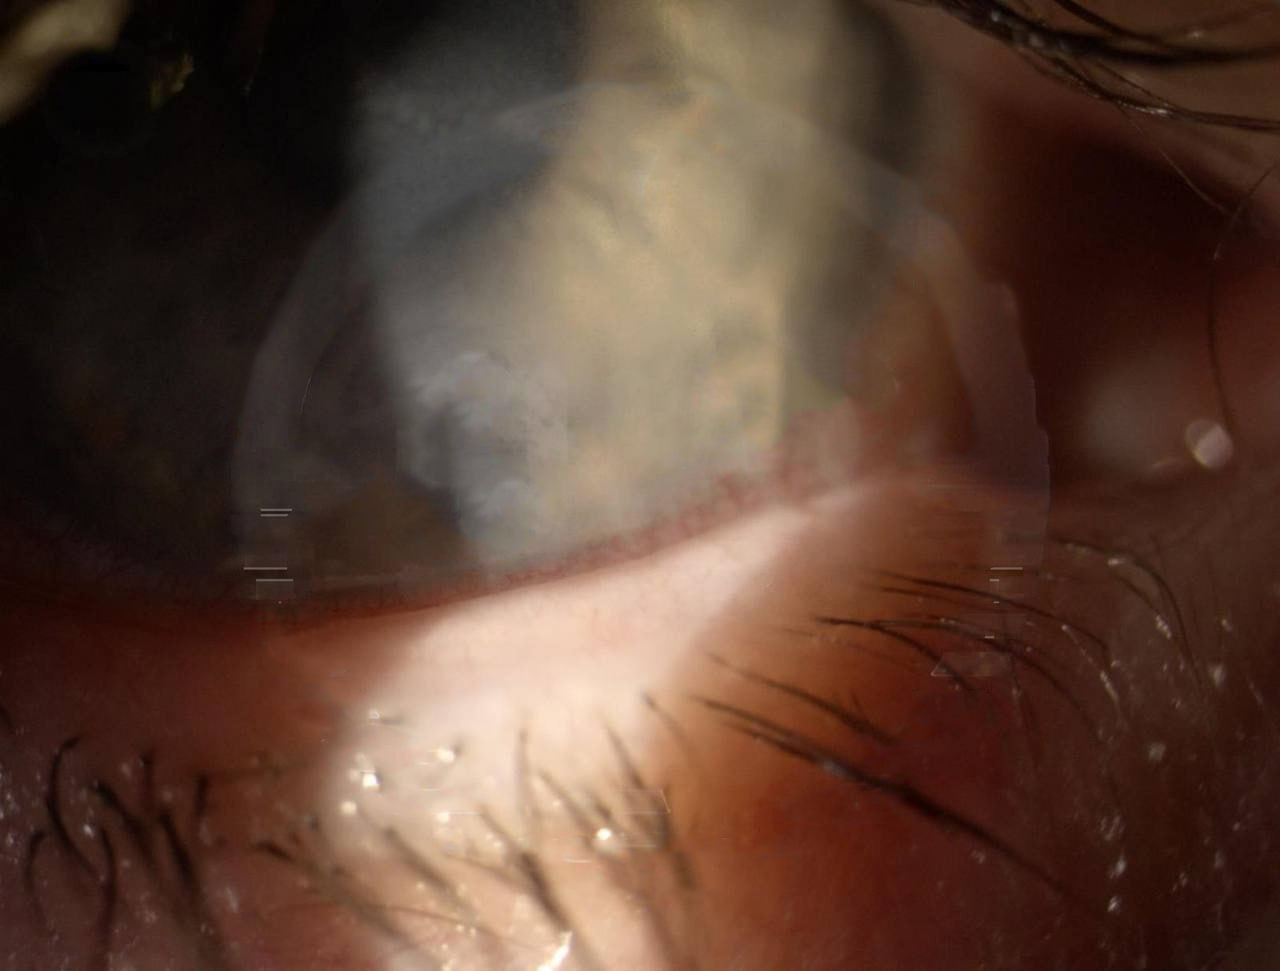

Москвичка ослепла после блефаропластики.

46-летняя жена президента Федерации еврейских общин Бороды сделала операцию по изменению формы век 23 октября, и почти сразу начались проблемы.

Женщину выписали спустя неделю в плохом состоянии: глаза не закрывались, и боль была невыносимой. Клиника прописала капли, от которых она начала слепнуть. Другой врач диагностировал отслоение роговицы, и женщине срочно потребовалась помощь в Италии. Итальянский хирург смог вернуть зрение лишь на одном глазу и всего на 30%. Впереди еще ряд операций.